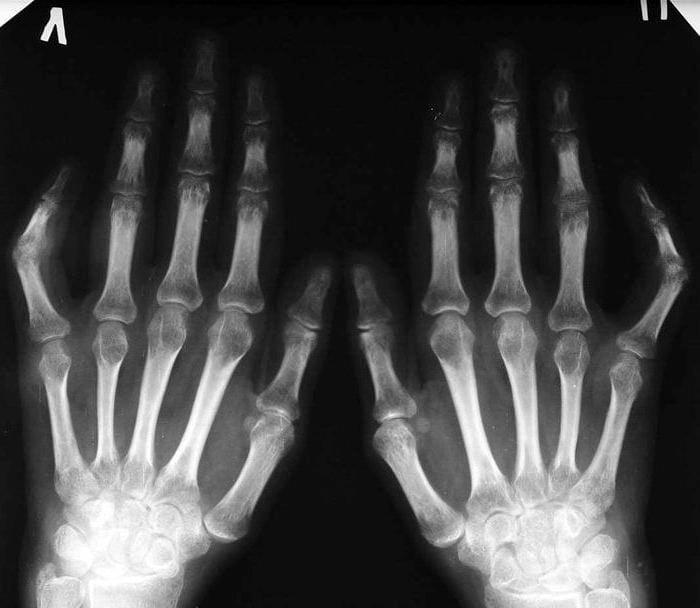

В ревматологической практике существует перечень маркеров, при обнаружении большей части которых выставляется диагноз «ревматоидный серонегативный артрит». Это время развития РА, количество пораженных суставов, выявление характерных округлых узелков, наличие эрозий и декальцификации костных тканей в сочленениях кистей со сформировавшимися кистами. Несмотря на отсутствие самого специфического маркера, остальные симптомы позволяют выявить серонегативный РА при обнаружении повышенного уровня скорости оседания эритроцитов и IgA.

Помимо признаков развития остеопороза, рентгенологическое исследование помогает выявить:

- частичное, а иногда полное сращивание суставных щелей;

- истончение и разрушение гиалиновых хрящей;

- ассиметричное расположение пораженных патологией суставов.